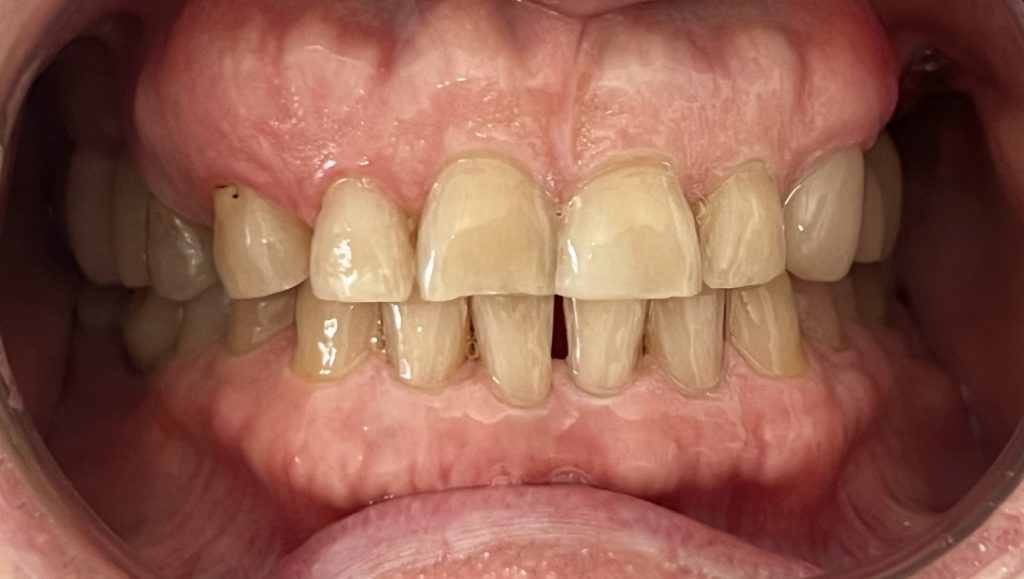

The aim is to improve your health, chewing function and/or aesthetic appearance and once healing and restoration is complete you will be able to enjoy a wide variety of foods again.

- A single tooth is missing – Crowns